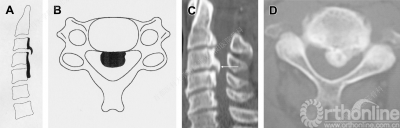

硬膜骨化(Dural ossification, DO)是后纵韧带骨化的一种特殊类型,它是由于骨化形成过程扩展到临近硬膜而导致临近硬膜骨化。DO的发生率约占OPLL的10%。根据DO的影像学形态特点,可以进一步将其分为以下三类:

孤立型:

双层型:

团块型:

术前了解DO的形态是很重要的,可以有效避免术中不必要的硬膜损伤。